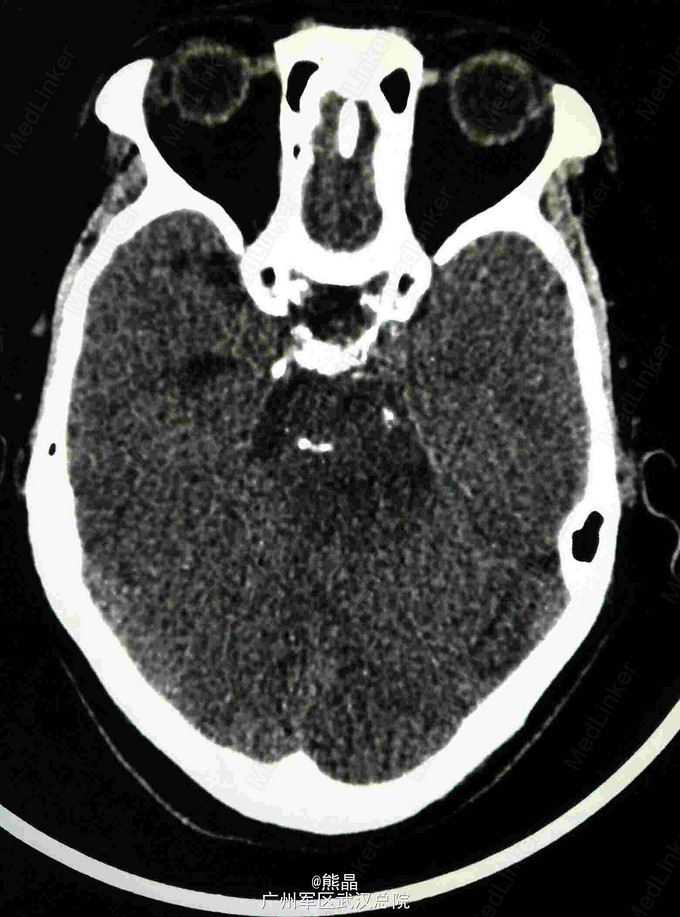

查体:左上肢屈曲状态,不能伸直 CT:碟鞍区及脑干区可见大片状密度减低影,右侧碟鞍骨质有破坏征象 MRI:肿块呈长T1长T2信号,增强呈蜂窝状强化